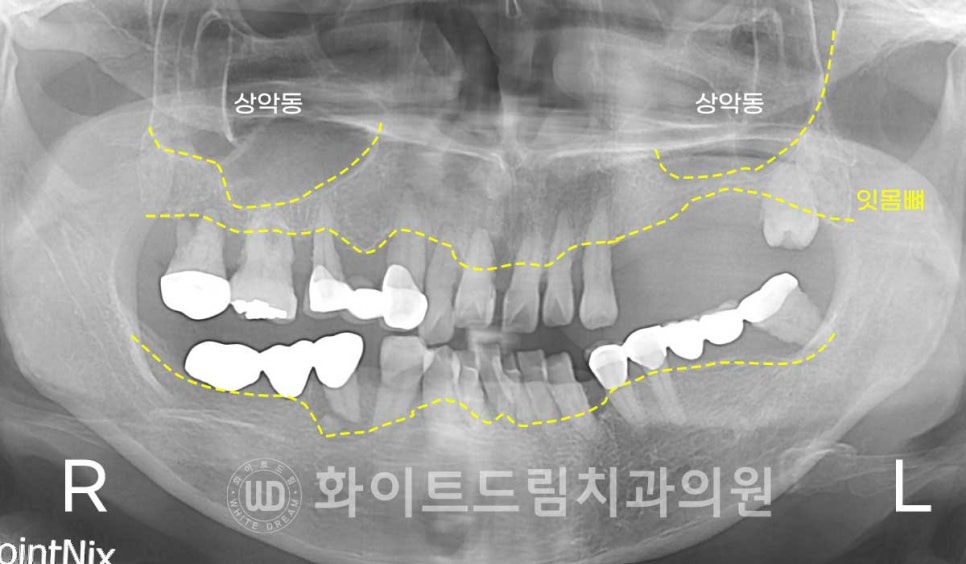

X-RAY 사진을 보면

전체적으로 잇몸뼈가 많이 녹아내려있고,

치아가 없는 오른쪽 상악 어금니 부위의 골 흡수가 크게 진행된 것을 보실 수 있습니다.

임플란트는 잇몸뼈와 유착되어 강한 저작력을 발휘하는 치료 방법으로

잇몸뼈의 상태에 영향을 많이 받습니다.